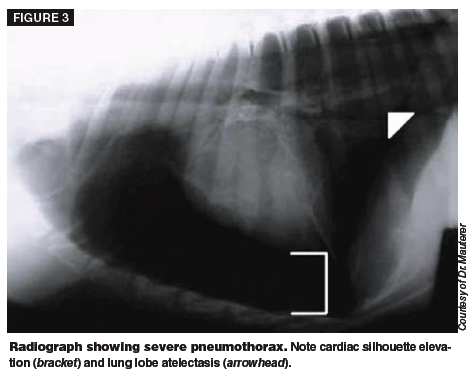

Describe the radiographic findings shown here.

What condition is associated with such findings?

What factors can cause decreased opacity of the lungs on radiograph?

Name three conditions which can cause diffuse or focal decreases in radiographic lung opacity.